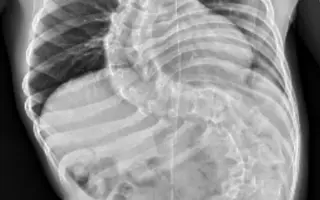

Těžká skolióza

Velký zdravotní problém, který s DMO souvisí, je těžká a život ohrožující skolióza. Ronji křivka je 115 stupňů, což znamená, že je úplně zlomená v pase a utlačuje plíce a vnitřní orgány. Operace je natolik náročná a v jejím případě také tolik riskantní, že se k ní lékaři neodvážili a nebo ji vůbec nedoporučují. Od 5. měsíce cvičila Ronja Vojtovu metodu, podstoupila několikrát lázeňskou léčbu a řadu neurorehabilitací. Nyní prochází růstovým spurtem a její pohyb potřebuje výraznou podporu.